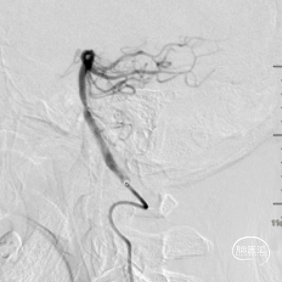

术前造影,BA近端闭塞。

术前造影,LC7次全闭塞。

术前造影,RICA 通过交通动脉向左侧颈内动脉及基底动脉尖代偿供血。

微导管造影。

支架释放后发现远段大负荷血栓影,近端狭窄,狭窄不解除,远端血栓很难清除。